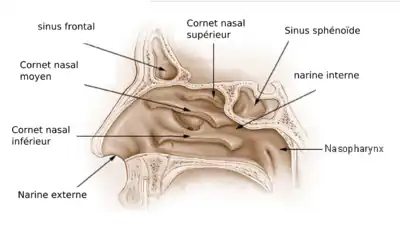

Les cavités nasales ou fosses nasales sont deux espaces séparés par une cloison : le septum nasal. Elles sont situées :

Limites

Les fosses nasales sont limitées par :

- l'orifice piriforme en avant,

- l'orifice choane en arrière,

- l'os nasal et l'ethmoïde en haut,

- le maxillaire, l'ethmoïde et le cornet nasal inférieur latéralement,

- le palais (os maxillaire et os palatin), qui les sépare de la cavité buccale.

À l'origine cavité unique chez les vertébrés primitifs, la cavité est séparée médialement en 2 fosses par une cloison verticale, le septum nasal, constitué des os vomer et ethmoïde.

Les fosses nasales sont prolongées en avant par le nez et en arrière par le pharynx.

Les sinus paranasaux sont reliés aux fosses nasales par des petits orifices appelés ostia.

Sur les côtés latéraux on a trois cornets qui offrent une résistance à l'écoulement de l'air et le dirigent vers l'épithélium olfactif en haut.

Il y a trois cornets dans chaque cavité nasale :

- le cornet inférieur : le plus grand, aussi long que l'index;

- le cornet moyen : aussi long qu'un auriculaire ;

- le cornet supérieur : très petit.

Les deux cavités nasales sont séparées par la cloison nasale appelée septum.

Les cornets divisent les voies respiratoires nasales en 3 passages aériens semblables à des sillons, les méats inférieur, moyen et supérieur, forçant ainsi l'air turbulent à s'écouler selon un flux laminaire autour de la plus grande surface possible de cils et de tissu. Les cornets sont essentiellement le radiateur et le moteur du nez.

La majeure partie du flux d'air inhalé voyage dans le méat moyen, entre les cornets inférieurs et les cornets moyens.

Les cornets moyens sont plus petits et se projettent vers le bas à partir des sinus ethmoïdes. Ils abritent les ouvertures jusqu'aux maxillaires et aux sinus ethmoïdes et agissent comme des tampons d'air pour que les sinus ne soient pas en contact direct avec le flux d'air pressurisé nasal.

Les cornets supérieurs protègent le bulbe olfactif et sont également innervés avec une multitude de terminaisons nerveuses olfactives qui se prolongent quelque part dans les cornets moyens.